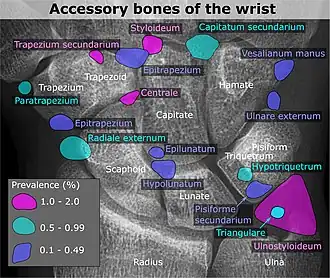

Wrist and hand

| Accessory bone | Prevalence on the right (R) and left (L)[5] |

|---|---|

| Os ulnostyloideum | 1.5% R, 2.4% L |

| Os centrale | 1.3% R, 2.1% L |

| Os trapezium secundarium | 0.5% R, 2.1% L |

| Os styloideum | 1.2% R, 1.2% L |

| Os radiale externum | 1% R, 0.9% L |

| Os triangulare | 1% R, 0.9% L |

| Os paratrapezium | 0.3% R, 0.9% L |

| Os capitatum secundarium | 0.8% R, 0.3% L |

| Os Hypotriquetrum | 0.5% R |

| Os hypolunatum | 0.3% L |

| Os epilunatum | 0.3% R, 0.3% L |

| Os ulnare externum | 0.3% L |

| Os pisiforme secundarium | 0.3% R |

| Os epitrapezium | 0.3% L |

| Os vesalianum manus | 0.3% L |